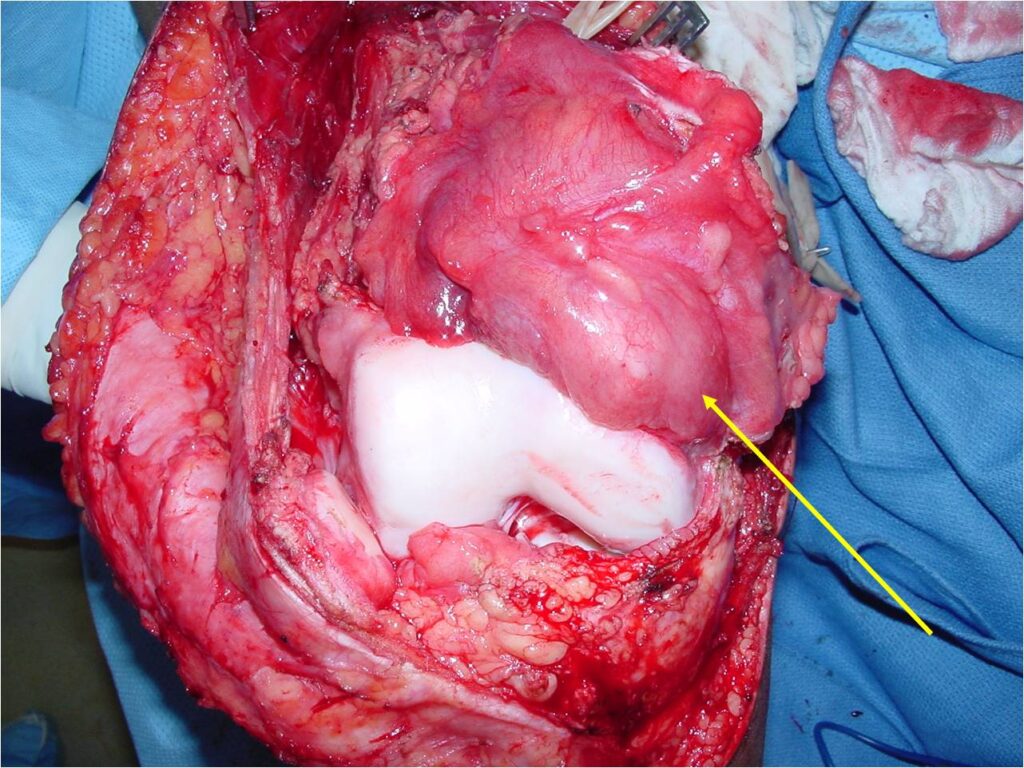

Gross Pathology

- Grossly lobulated, gray-white, translucent

- Calcification is common

- Underlying cortex eroded with irregular sclerotic reaction

- Wide Limb Sparing Resection whenever feasible